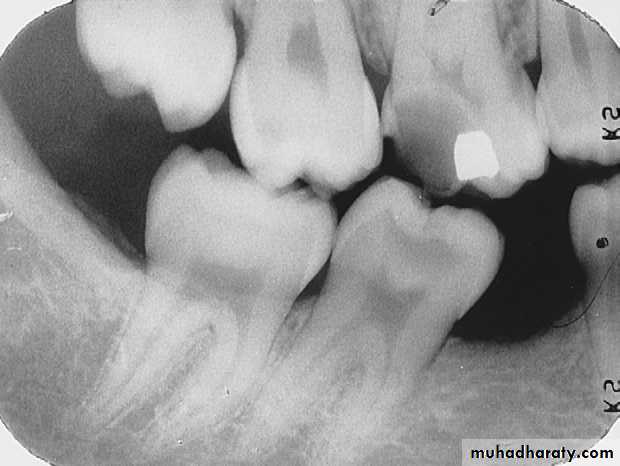

extends through enamel, through dentin, and more than half the distance toward the pulpSevere Interproximal Caries

A severe carious lesion on the distal surface of the mandibular first molar.

Severe lesion